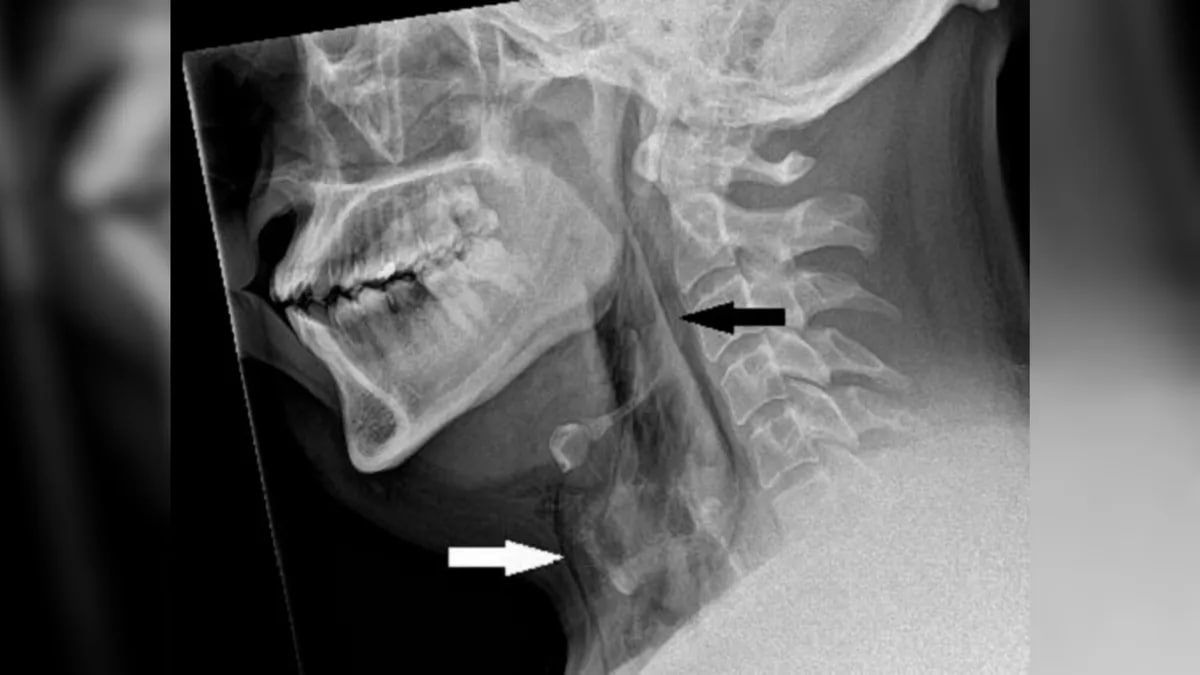

Чоловік років 30 вів машину, коли відчув позив чхнути. Він придушував чхання, затискаючи ніс і закриваючи рот, але одразу ж відчув сильний біль у шиї. Коли він звернувся у відділення невідкладної допомоги, комп'ютерна томографія його шиї та грудної клітки виявила розрив трахеї завдовжки в півсантиметра.

Лікарі відмовилися від операції, оскільки в іншому життєві показники чоловіка були нормальними. Проте пацієнт залишився під наглядом. Через п'ять тижнів після виписки подальша комп'ютерна томографія показала, що його трахея зажила.

"Ми підозрюємо, що трахея перфорувалася через швидке підвищення тиску в трахеї під час чхання із затиснутим носом і закритим ротом", - написала команда медиків, порадивши людям не придушувати чхання в такий спосіб.